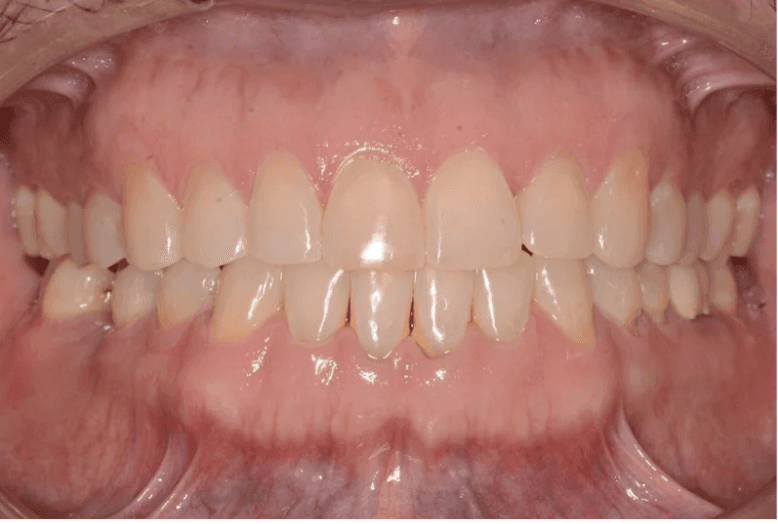

Final results

INTRAORAL